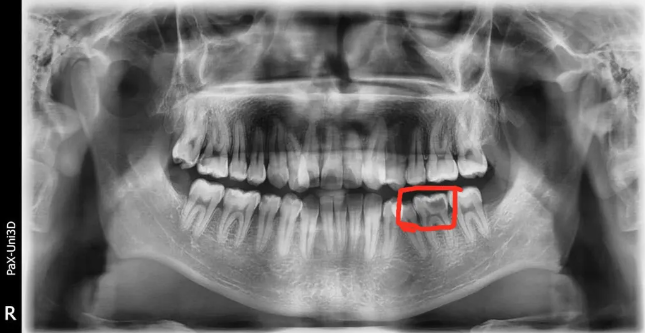

🔎智齿

△全口牙齿一般有28-32颗,在牙片上从中间牙齿往后数第八颗就是智齿。